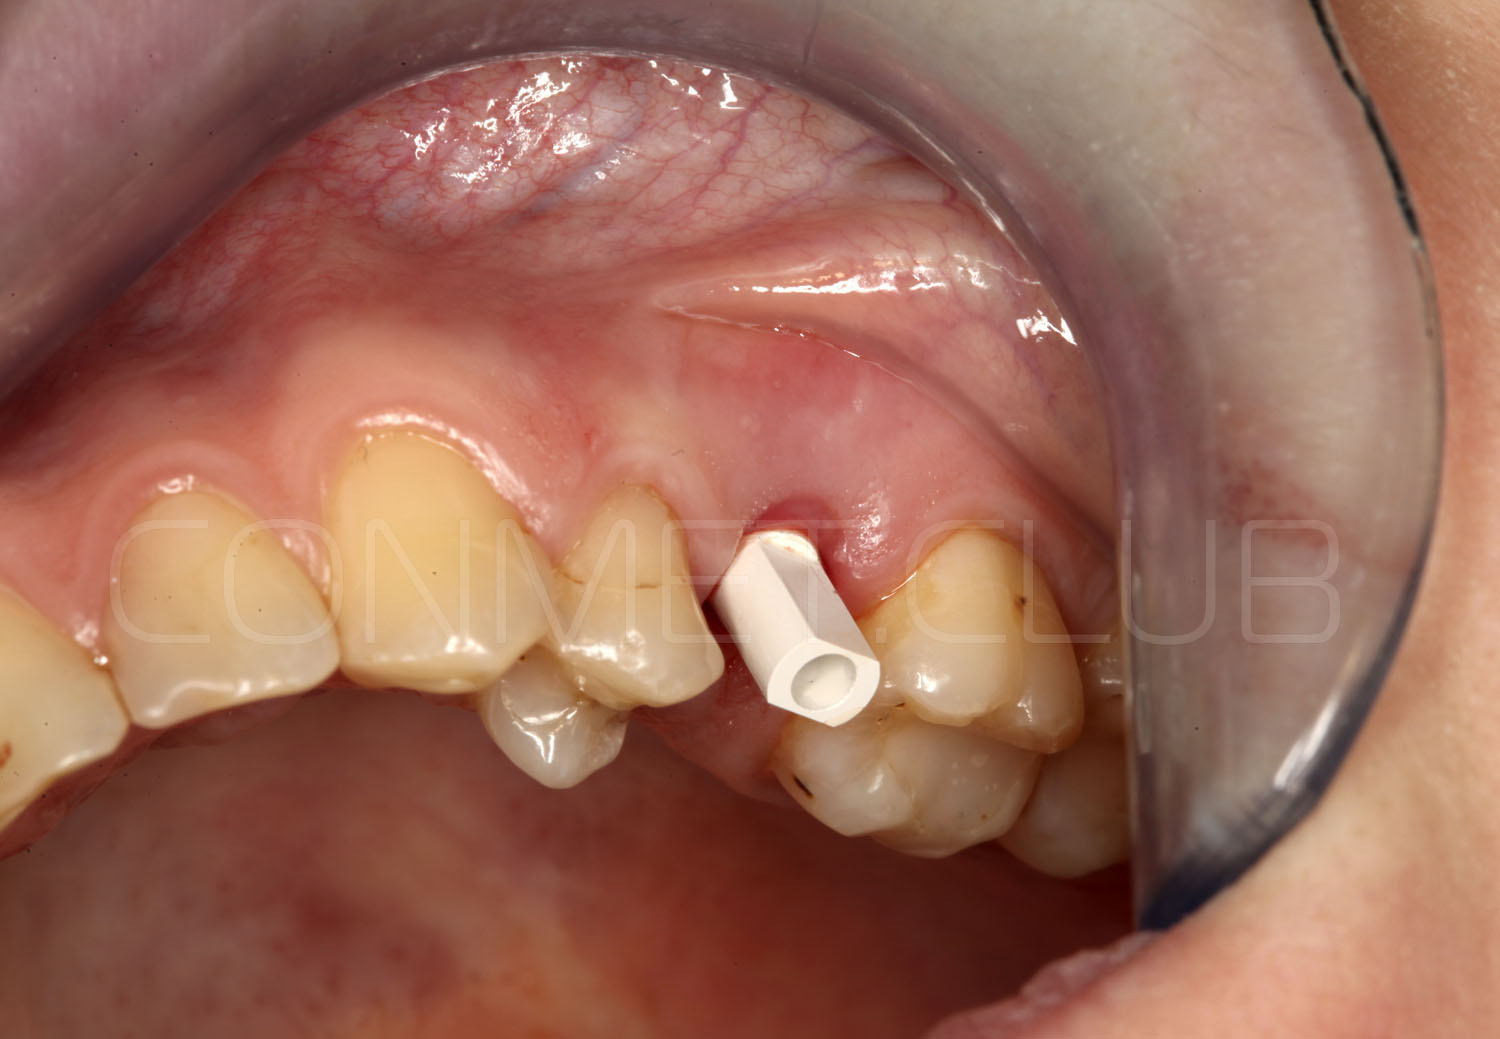

Направляющие втулки нового типа имеют цветовую маркировку (с диаметром отверстия 2,2 мм - серебристого цвета и 2,8 мм - золотистого цвета), а также одинаковый внешний диаметр, что позволяет использовать 2 одинаковых шаблона, но с втулками разного диаметра.

Характерной особенностью новых втулок является их фиксация в шаблон без использования клеев или адгезивов. Это значительно упрощает работу при фиксации втулок в шаблон и абсолютно исключает попадание фиксирующего клея внутрь втулок.

Через 8 недель проводится внутриротовое сканирование. Зафиксирован сканмаркер, который позволяет перенести данные сканирования в виде STL файла в программу ExoCad, осуществить моделирование индивидуального абатмента и выточить его на фрезерном станке.

Для уменьшения артефактов возникающих при сканировании и максимально точного сопоставления в программе ExoCad рекомендуем использовать оригинальные сканмаркеры фирмы Конмет.